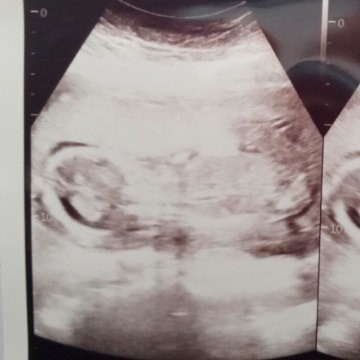

Hasil Usg belum terlihat baru terlihat rahim yang membesar

Momy2 mohon bantu jawab atau share pengalaman ya barangkali ada yg sama. Ini kehamilan saya.. HPHT saya 31 Januari 2021 harusnya 5 minggu namun saya periksa ke bidan USG baru terlihat rahim yg membesar saja. Kata bidan baru 3 minggu karena blm terlihat apa2 hanya rahim yang membesar. Hasil Testpack sudah positif garis dua bahkan 3 x saya test. Apakah ini wajar? Saya jd parno ketakutan sendiri. Mohon bantu share dan jawab ya momy2.... #seriusnanya #ingintahu #firstbaby #ingintahu